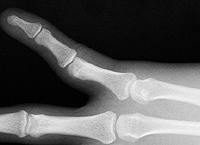

Вправление вывихов и подвывихов

Уменьшение вывихов и подвывиха. Закрытые манипуляции, предполагающие восстановление нормальных анатомических связей между суставными поверхностями костей со свежими травматическими вывихами и подвывихами различных локализаций. Обычно проводится под местной анестезией, в детстве, с повреждениями крупных суставов (например, бедер) и со значительным ограничением травм, указывается общая анестезия. Восстановление осуществляется по определенному алгоритму, который зависит от типа дислокации. После устранения повреждения выполняется иммобилизация до слияния связок, окружающих сустав (обычно около 3 недель).